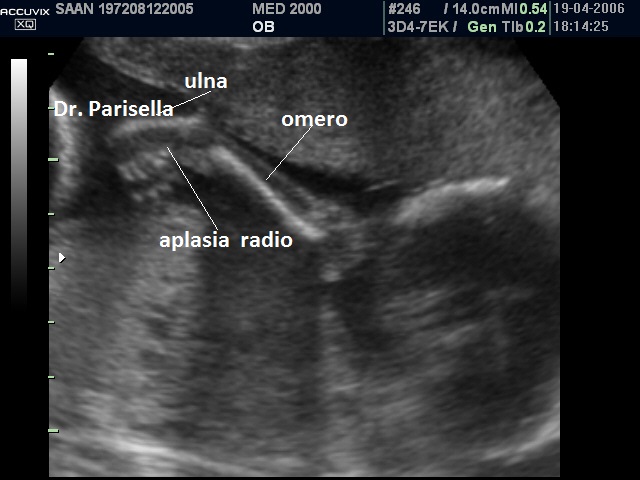

La Sindrome di Gershoni-Baruch รจ una rara malformazione congenita multipla caratterizzata da onfalocele, ernia diaframmatica, anomalie cardiovascolari e difetti radiali.